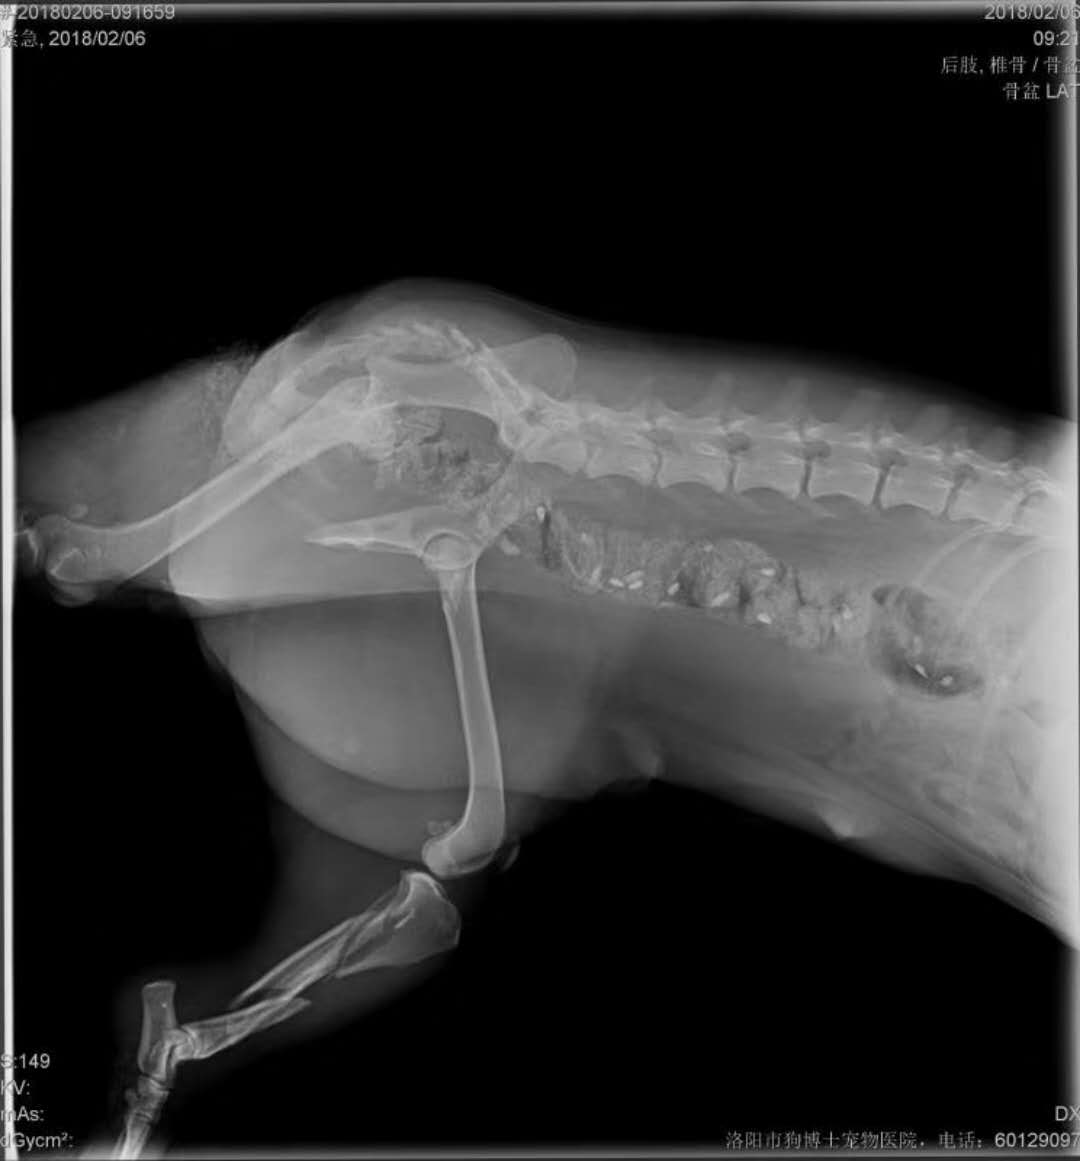

今天救助的粉碎性骨折的狗狗化驗(yàn)單,病情比較嚴(yán)重,先需要輸血,恢復(fù)體質(zhì),然后才能手術(shù),感謝大家的關(guān)注。